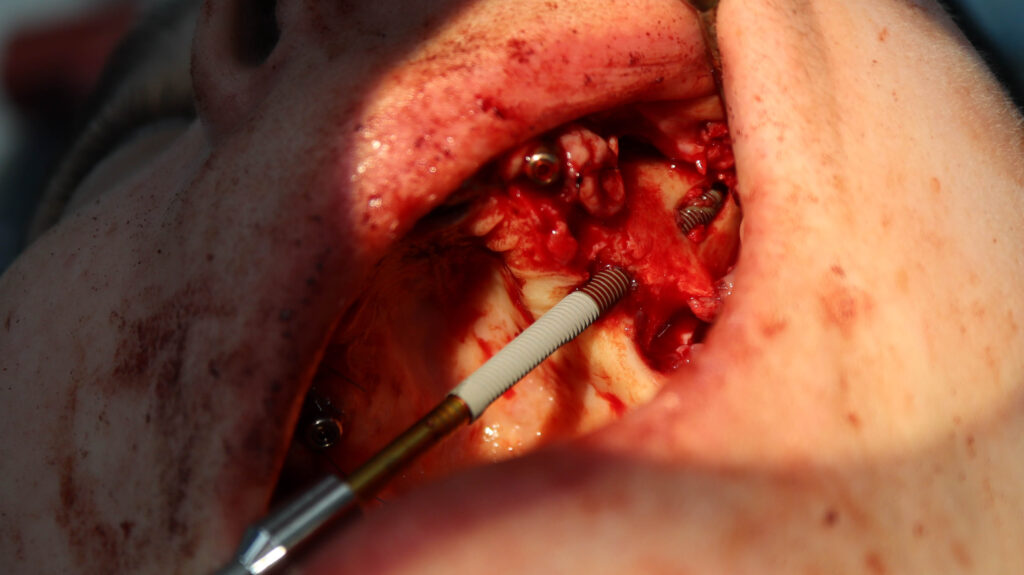

процесс работы

Что было сделано:

На верхней челюсти были удалены зубы, которые находились в неудовлетворительном состоянии, проведена комплексная имплантация по системе All-on-6, установлены 4 имплантата Megagen AnyOne и 2 скуловых имплантата NeoDent.

Фиксации имплантата внутри костной ткани (торк).

процесс имплантации